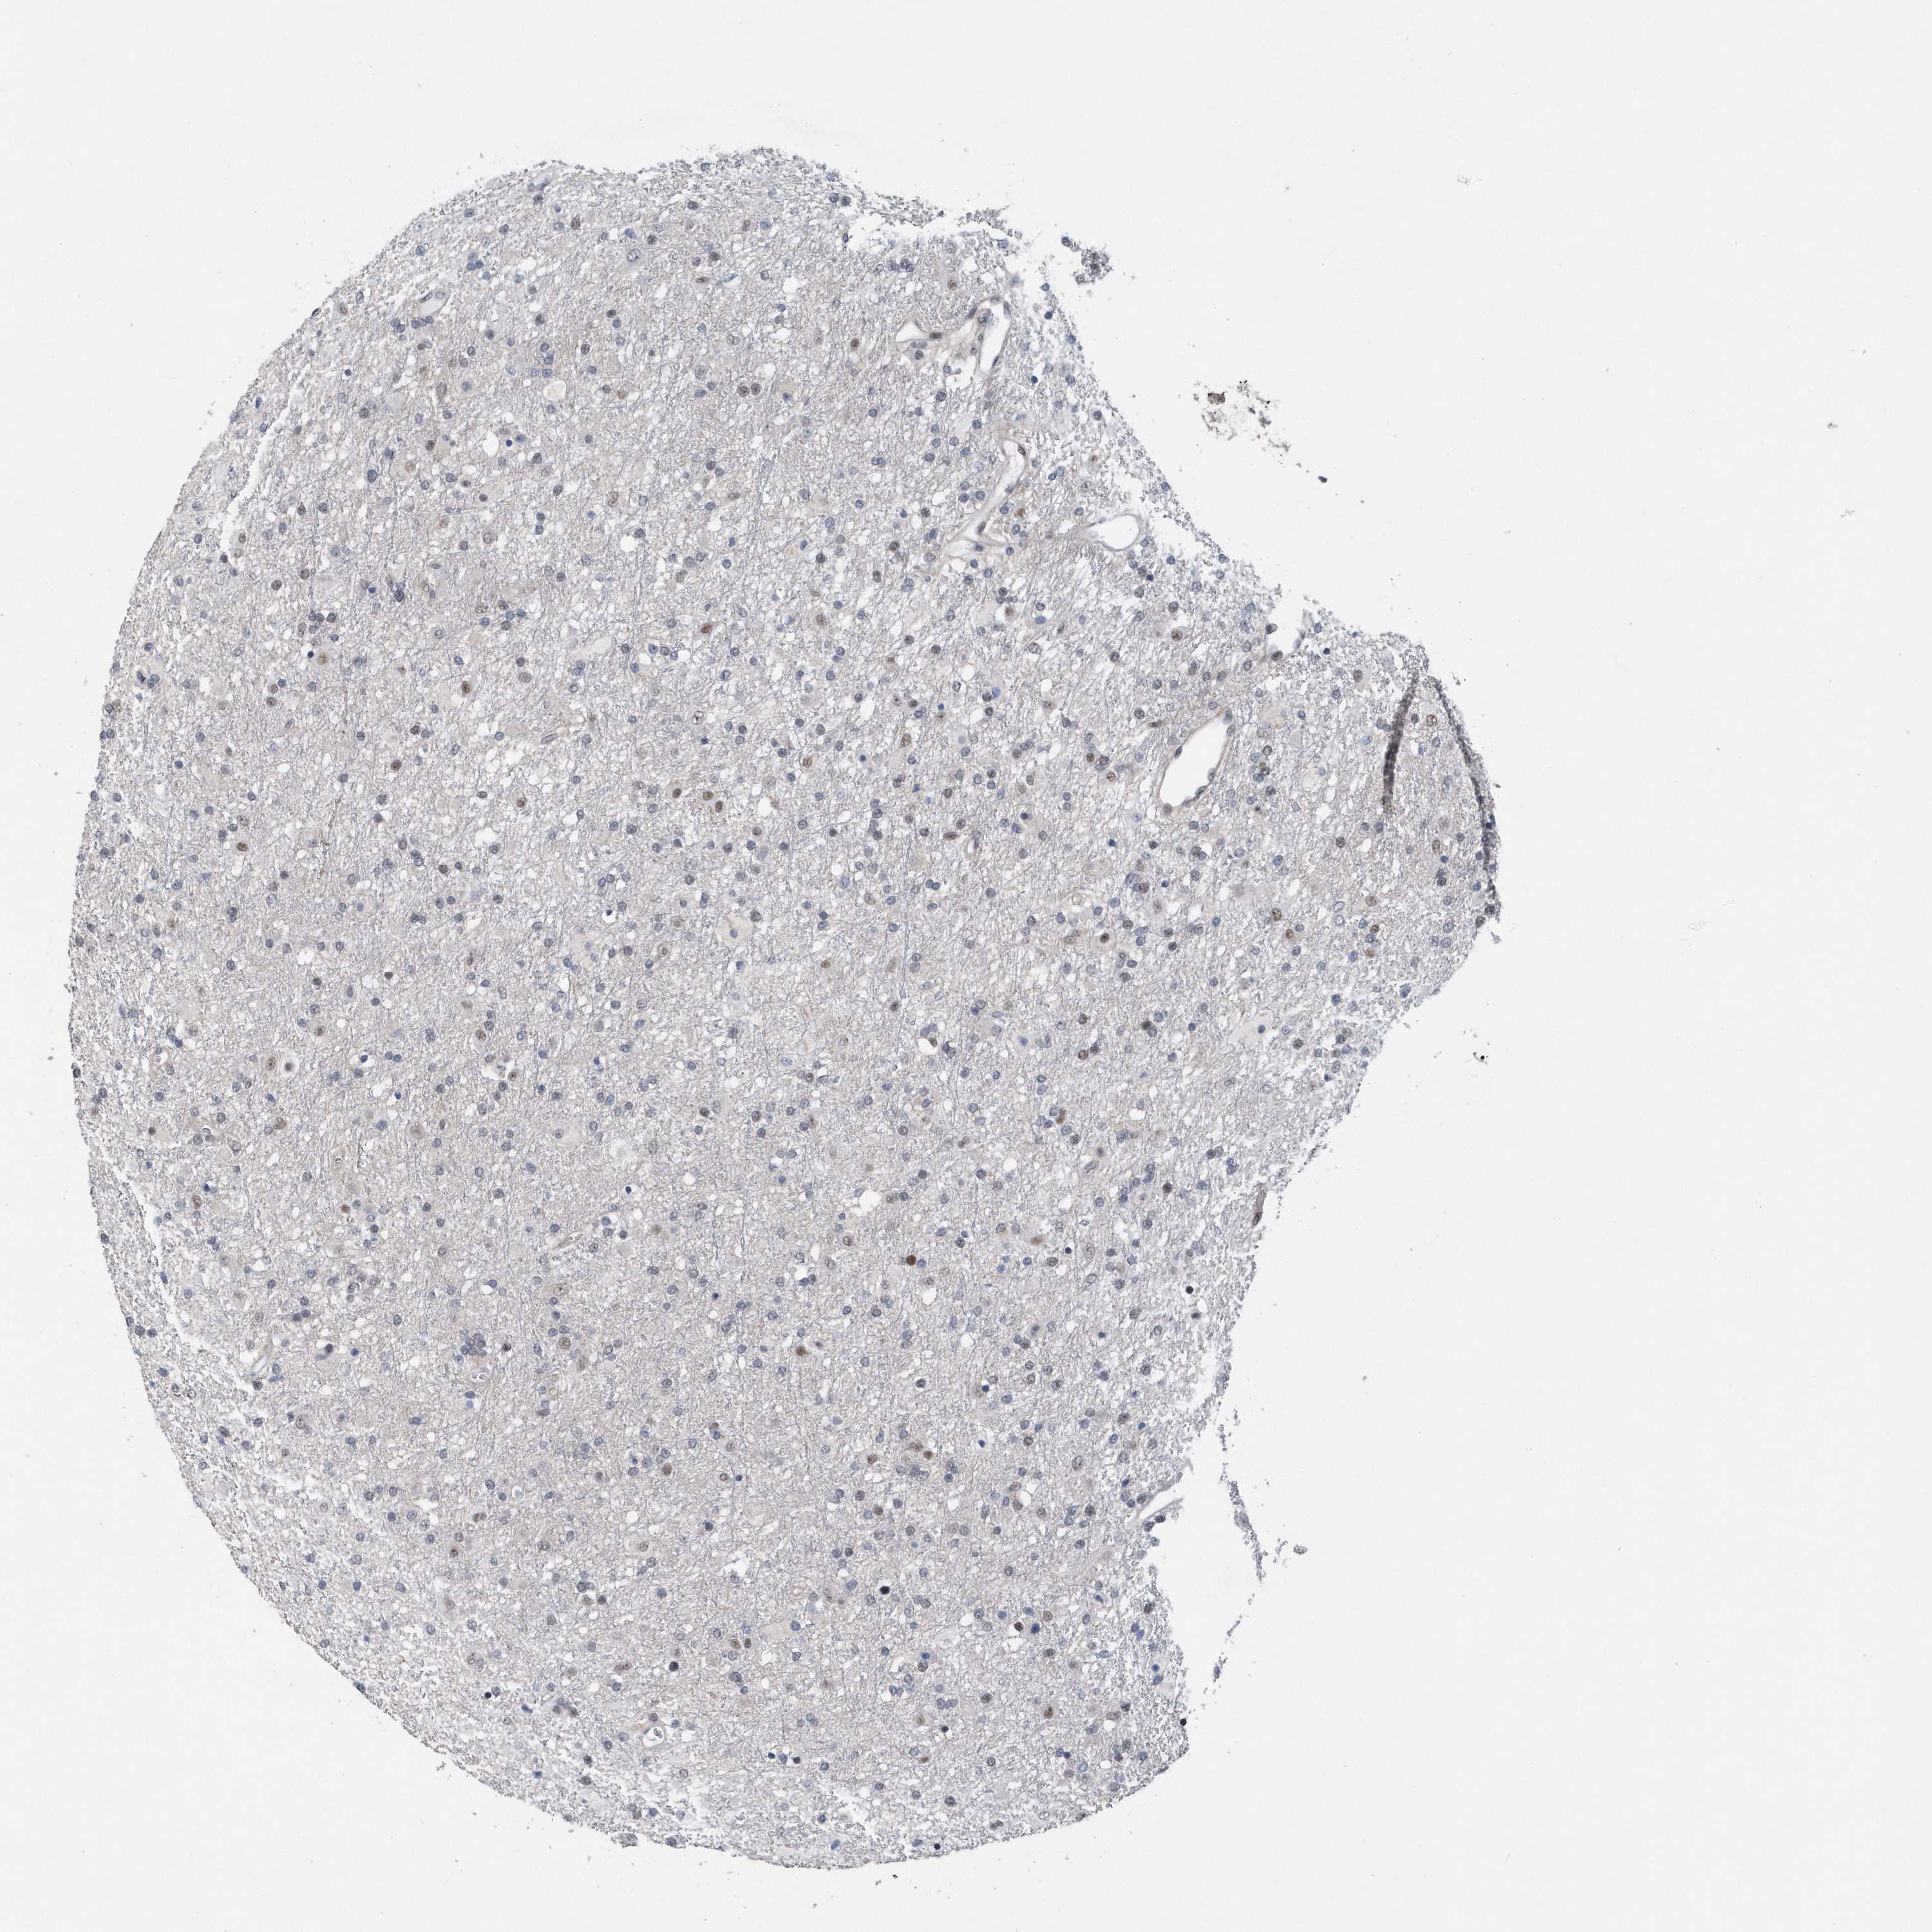

GLIOMA - Protein expressioni

A mouse-over function shows sample information and annotation data. Click on an image to view it in a full screen mode. Samples can be filtered based on level of antibody staining by selecting one or several of the following categories: high, medium, low and not detected. The assay and annotation is described here.

Note that samples used for immunohistochemistry by the Human Protein Atlas do not correspond to samples in the TCGA dataset.

Antibody stainingi

Antibody staining in the annotated cell types in the current human tissue is reported as not detected, low, medium, or high, based on conventional immunohistochemistry profiling in selected tissues. This score is based on the combination of the staining intensity and fraction of stained cells.

Each image is clickable and will lead to virtual microscopy that enables deeper exploration of all samples and also displays staining intensity scores, fraction scores and subcellular localization as well as patient and tissue information for each sample.

Antibody HPA037578

Staining

High

Medium

Low

Not detected

Intensity

Strong

Moderate

Weak

Negative

Quantity

>75%

75%-25%

<25%

None

Location

Nuclear

Cytoplasmic/membranous

Cytoplasmic/membranous,nuclear

Glioma, malignant, High grade

Glioma, malignant, Low grade

Glioblastoma, NOS